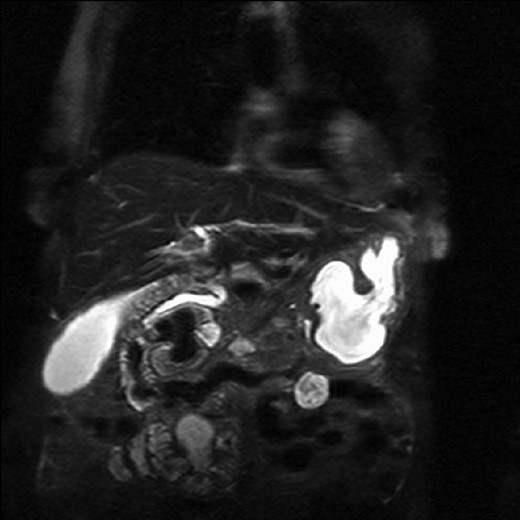

The patient underwent an MRCP which demonstrated mild distension of the gallbladder with several calculi. There was intra- and extra-hepatic biliary dilatation to the level of the ampulla. A very large fluid and air filled periampullary duodenal diverticulum measuring ~8 cm in the long axis was also noted (Figs 1–3). This finding was unchanged compared to a CT study from 6 months previously. The CBD was dilated to the level of this diverticulum and the cause of the patient’s biliary dilatation and obstruction. Interestingly, an unusual appearance to the kidneys was recorded with multiple microcystic changes in both kidneys, which is typically reported in patients with lithium induced renal disease. A gastroduodenoscopy revealed a large periduodenal diverticulum in D2 (Fig. 4).